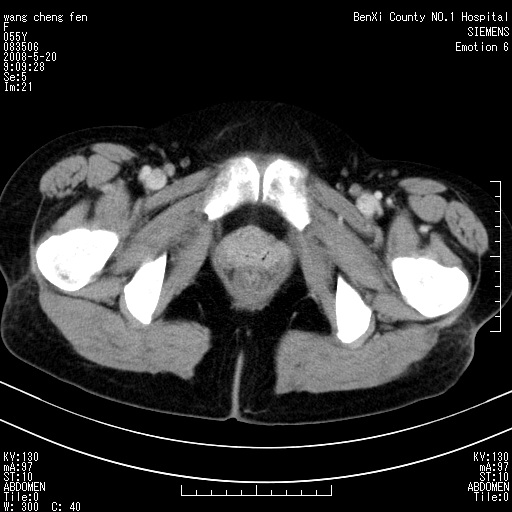

女、绝经后阴道流血3个月

左侧附件区可见一囊性占位,边缘清楚,内可见不规则形软组织影 ce:囊壁及内部可见强化 考虑 卵巢囊腺瘤

左侧附件区巨大囊实性病灶,边缘光整,病灶囊壁较厚,增强示囊壁及实性部分明显强化,强化呈度与宫体实质大致相同,宫腔积液征像,未见盆腔积液等其他异常,考虑左侧卵巢囊腺癌,不除外囊腺瘤及浆膜下肌瘤坏死

左侧附件区巨大囊实性病灶,边缘光整,病灶囊壁较厚,增强示囊壁及实性部分明显强化,强化呈度与宫体实质大致相同,宫腔积液征像,未见盆腔积液等其他异常。绝经后阴道流血3个月,结合病史左侧卵巢囊腺癌首先考虑,宫腔扩大不除外累及。期待结果。

支持浆膜下子宫肌瘤.之前由于网络原因未看全图片,现在重看,宫颈见一类圆形低密度影,增强轻度强化,低于肌层强化,宫腔扩大,考虑宫颈癌伴宫腔积液可能性大.